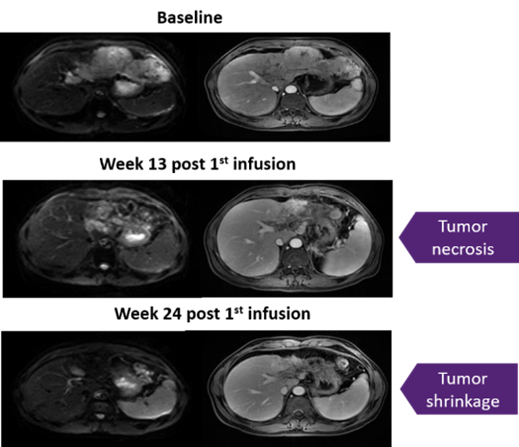

值得关注的是,其中1例患者疗效尤为突出:该患者第二剂输注后,肿瘤缩小同时出现ALT、GGT、AST及胆红素短暂3级升高,提示疗法具有明确靶向效应,且肝脏肿瘤显著缩小超30%,持续30个月(详见下图)。

▲图源“LIONTCR”,版权归原作者所有,如无意中侵犯了知识产权,请联系我们删除